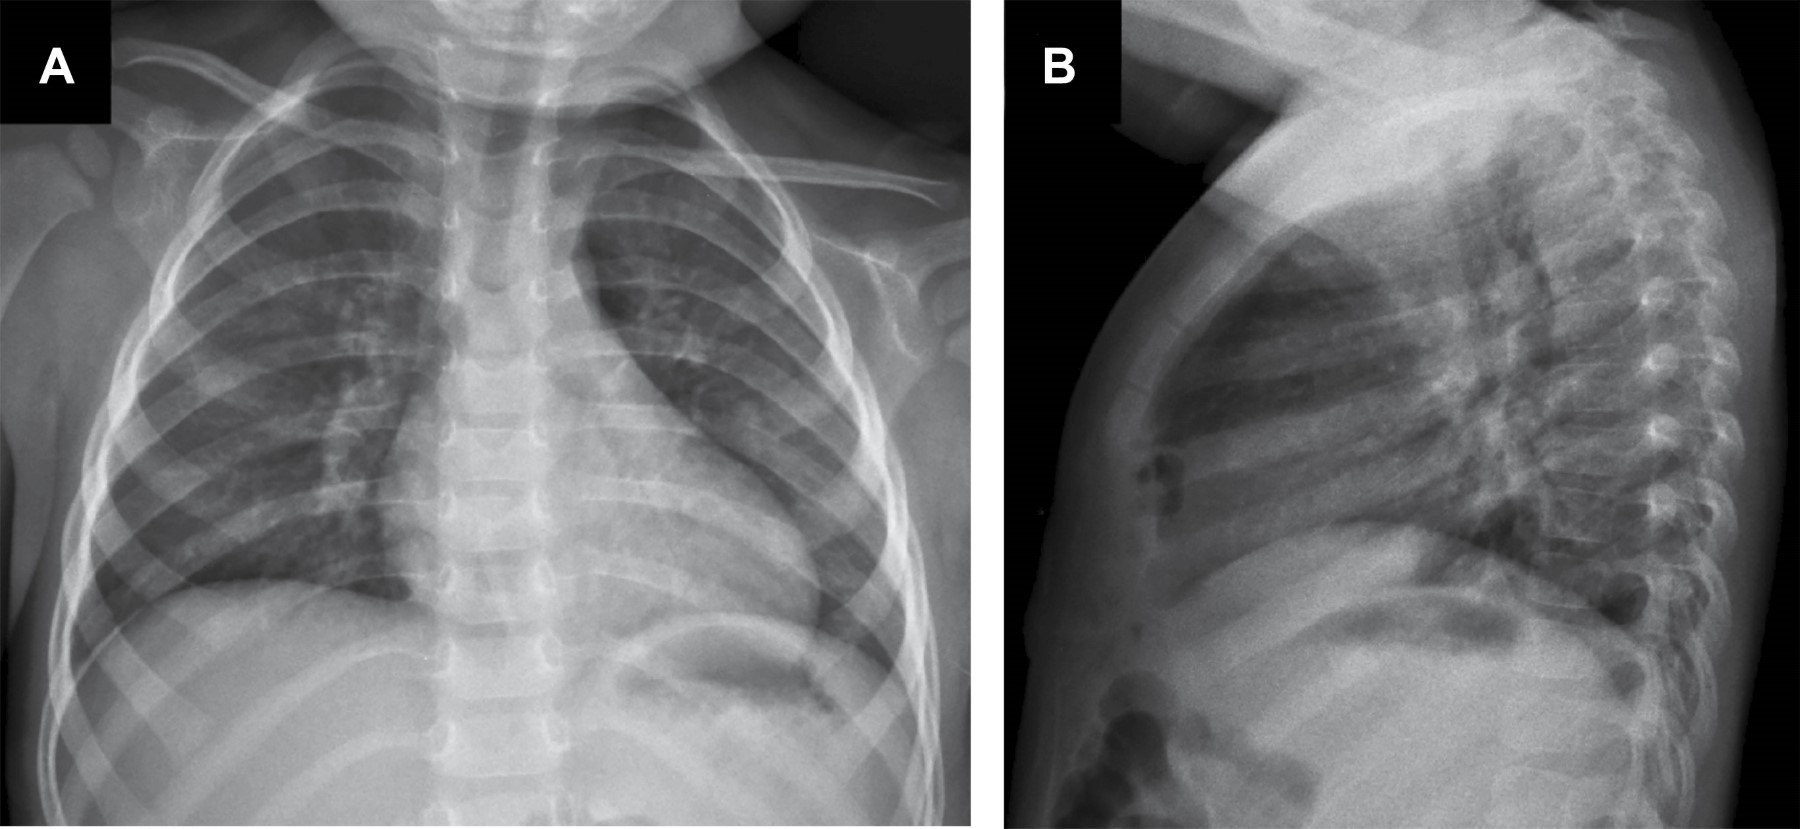

Morgagni-Larrey hernia: multimodal imaging evaluation and the importance of continuous surveillance

Morgagni-Larrey hernia, a rare congenital disability, poses challenges in its diagnosis and treatment. This article presents the case of a 24-month-old boy with a history of gastroesophageal reflux and recurrent pneumonia who presented with fever, persistent cough, and respiratory distress. Computed tomography (CT) and chest X-ray were essential in identifying an anterior diaphragmatic defect and protrusion of the transverse colon. Laparoscopic surgery, performed with the Hasson technique, allowed for precise repair of the defect with minimal invasions. The patient recovered without complications, highlighting the effectiveness of advanced imaging techniques and laparoscopy in managing this condition.

Figure 2